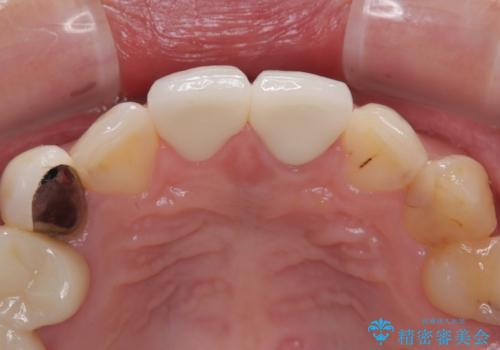

神経が露出しないよう慎重に行った結果、神経を保存することができました。処置後に多少の痛みが生じましたが、その後は良好な状態が続いています。

色、形ともに、自然な仕上がりとなり、患者様には大変満足していただきました。